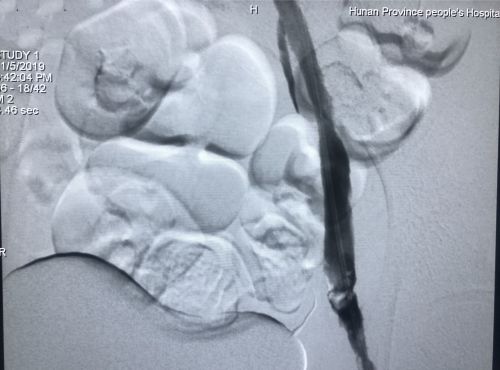

术后血管造影显示,深静脉通畅。